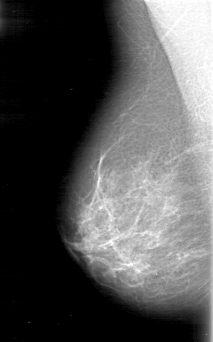

D_4054_1.RIGHT_CC

RIGHT_CC LINES 5206 PIXELS_PER_LINE 3301 BITS_PER_PIXEL 12 RESOLUTION 43.5 NON_OVERLAY